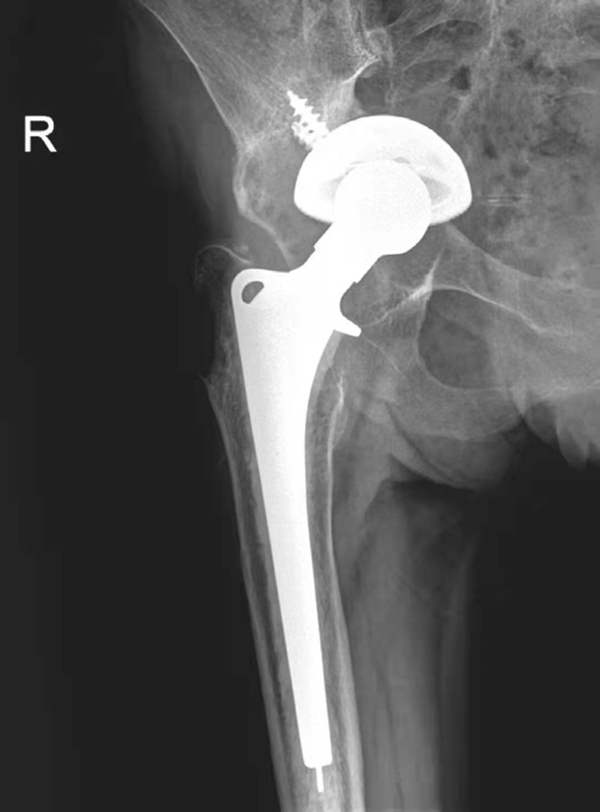

图3 无菌性松动

平片,示右侧髋臼杯周围骨质吸收,髋臼杯松动并向上内侧移位